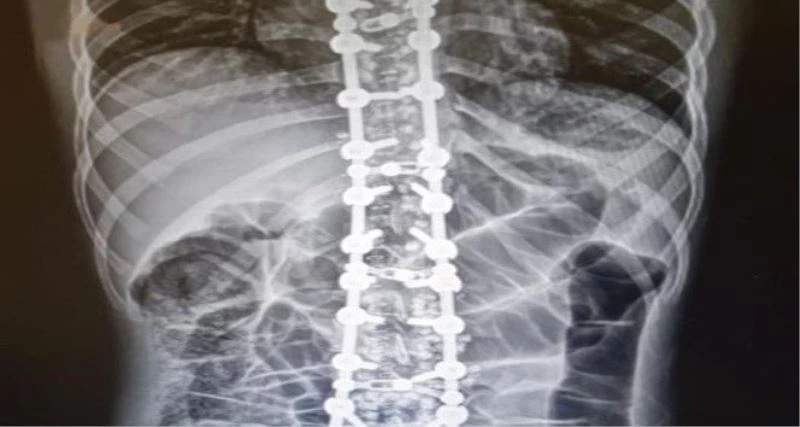

Osteopati vücudun her yerine uygulanabileceğini ancak en sık omurga problemlerinde kullanılmakta olduğunu ifade eden Özyurt, sözlerini şu şekilde sonlandırdı:

“Omurganın patolojik olarak saydığımız faset eklem kitlenmesi, omurgayı dik durmasını sağlayan kasların spazmı ve diğer omurga problemlerinde güvenle kullanabileceğimiz yöntemler bulunmaktadır. Duruş bozuklukları, omurga ve kas- iskelet sistemi hareket fonksiyon bozuklukları, omurga disk kaymaları, kuyruk sokumu problemleri, eklem sertliği, migren, gerilim tipi baş ağrısı, uyku bozuklukları, iç organ kaynaklı kas-iskelet sitemi ağrıları gibi çeşitli ve birçok hastalıkta osteopati kullanılabilir. Osteopatinin tedavi süresi probleme, yaşa ve kişiye göre değişebilmektedir.”